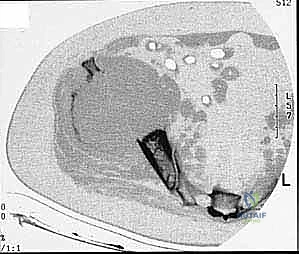

* CT with Intravenous Contrast and 3D Reconstruction (FIG 3): This is our workhorse for assessing bone involvement, destruction, and the critical relationship between the tumor and major pelvic blood vessels. It reveals any distortion of the pelvic anatomy and guides resectability. Figure 3A clearly shows extensive bone destruction and tumor extension into the pelvis and gluteal region. Figure 3C highlights an extensive tumor on the medial aspect of the ilium with destruction of the inner table.